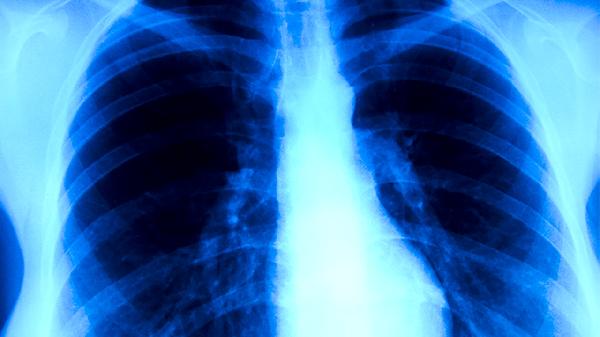

肺癌后期治疗需根据患者具体情况制定综合方案,主要包括姑息性放疗、靶向治疗、免疫治疗、对症支持治疗及心理干预。